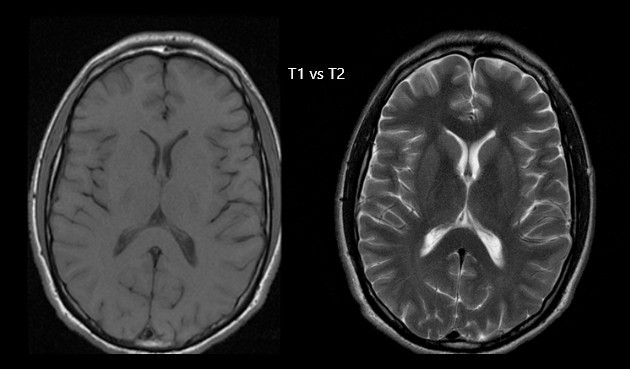

T1-weighted:

short TR and short TE (하얀색) 지방 - 간 - 백질 - 비장 - 회백질 - 근육 - 혈액 - 뇌척수액 - 물 (검은색)

T1 강조영상은 짧은 TR, TE 시간을 가지고 물이 검게 보이는 특성으로 다른 영상에 비해 찾기 쉬운 편입니다.

img.jpg

이에 반해, T2-weighted - long TR and long TE (하얀색) 물 - 뇌척수액 - 회백질 - 백질 (검은색)

T2 강조영상은 긴 TR, TE 시간을 가지고 물이나 혈액, 뇌척수액이 밝게 보이기 때문에 영상의 구분이 가능합니다.

Water

long T1 and T2 - dark in the T1-weighted image and bright in the T2-weighted image

MRI상에서 물은 긴 T1, T2를 가지므로 T1강조영상에서 검게 나타나고 T2강조영상에서는 밝게(고신호)로 나타납니다.

Tissue

short T1 and a long T2 - bright in the T1-weighted image and gray in the T2-weighted image.

조직은 짧은 T1과 긴 T2 이므로 T1 강조영상에서 밝게, T2 강조영상에서는 회색으로 보이는 것이 특징입니다.